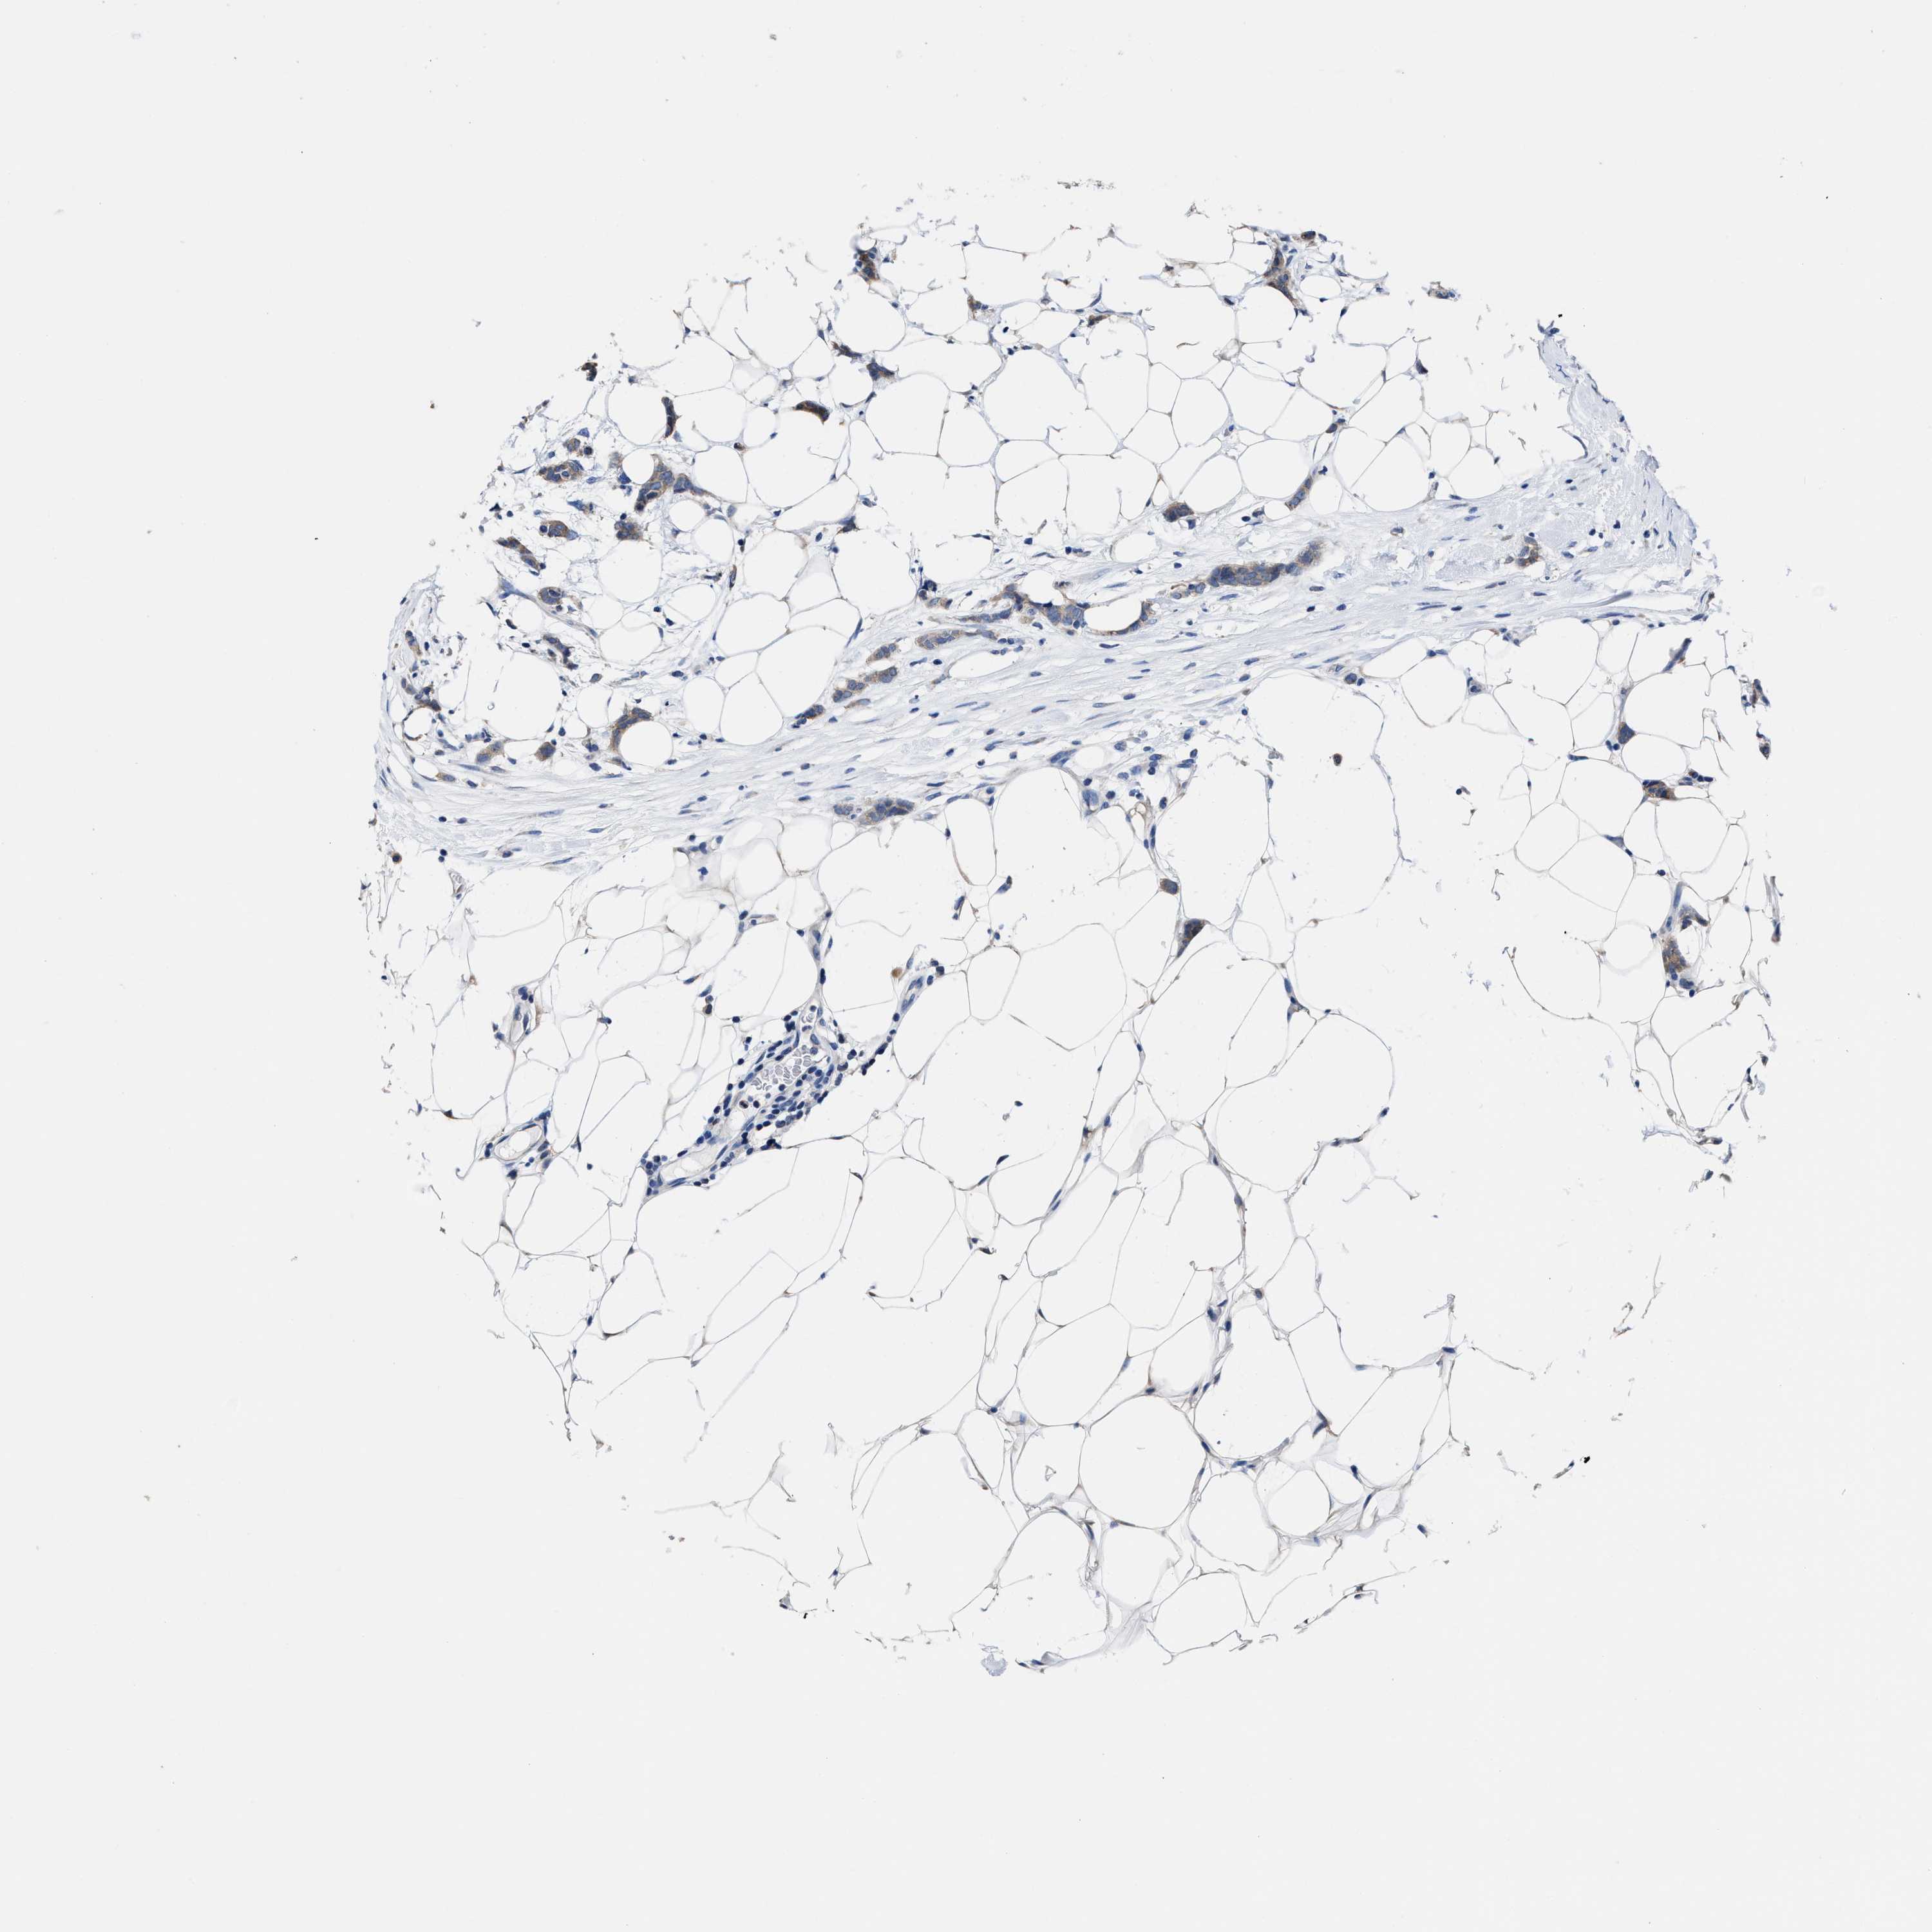

CANCER BREAST CANCER Show tissue menu

Breast cancer

Human cancer